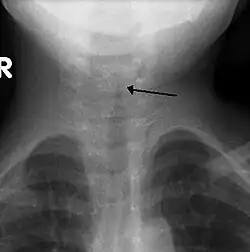

Kirchturm-Zeichen

Das Kirchturm-Zeichen (engl. steeple sign) ist ein radiologisches Zeichen, das eine subglottische Einengung der Luftröhre auf einer a.p.-Röntgenaufnahme zeigt. Es ist typisch für die subglottische Laryngotracheobronchitis (Pseudokrupp).[1]